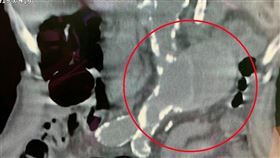

未爆彈!6.5cm「主動脈瘤」隨時索命

花蓮一名50多歲廖先生中風多年,去年因急性A型主動脈...